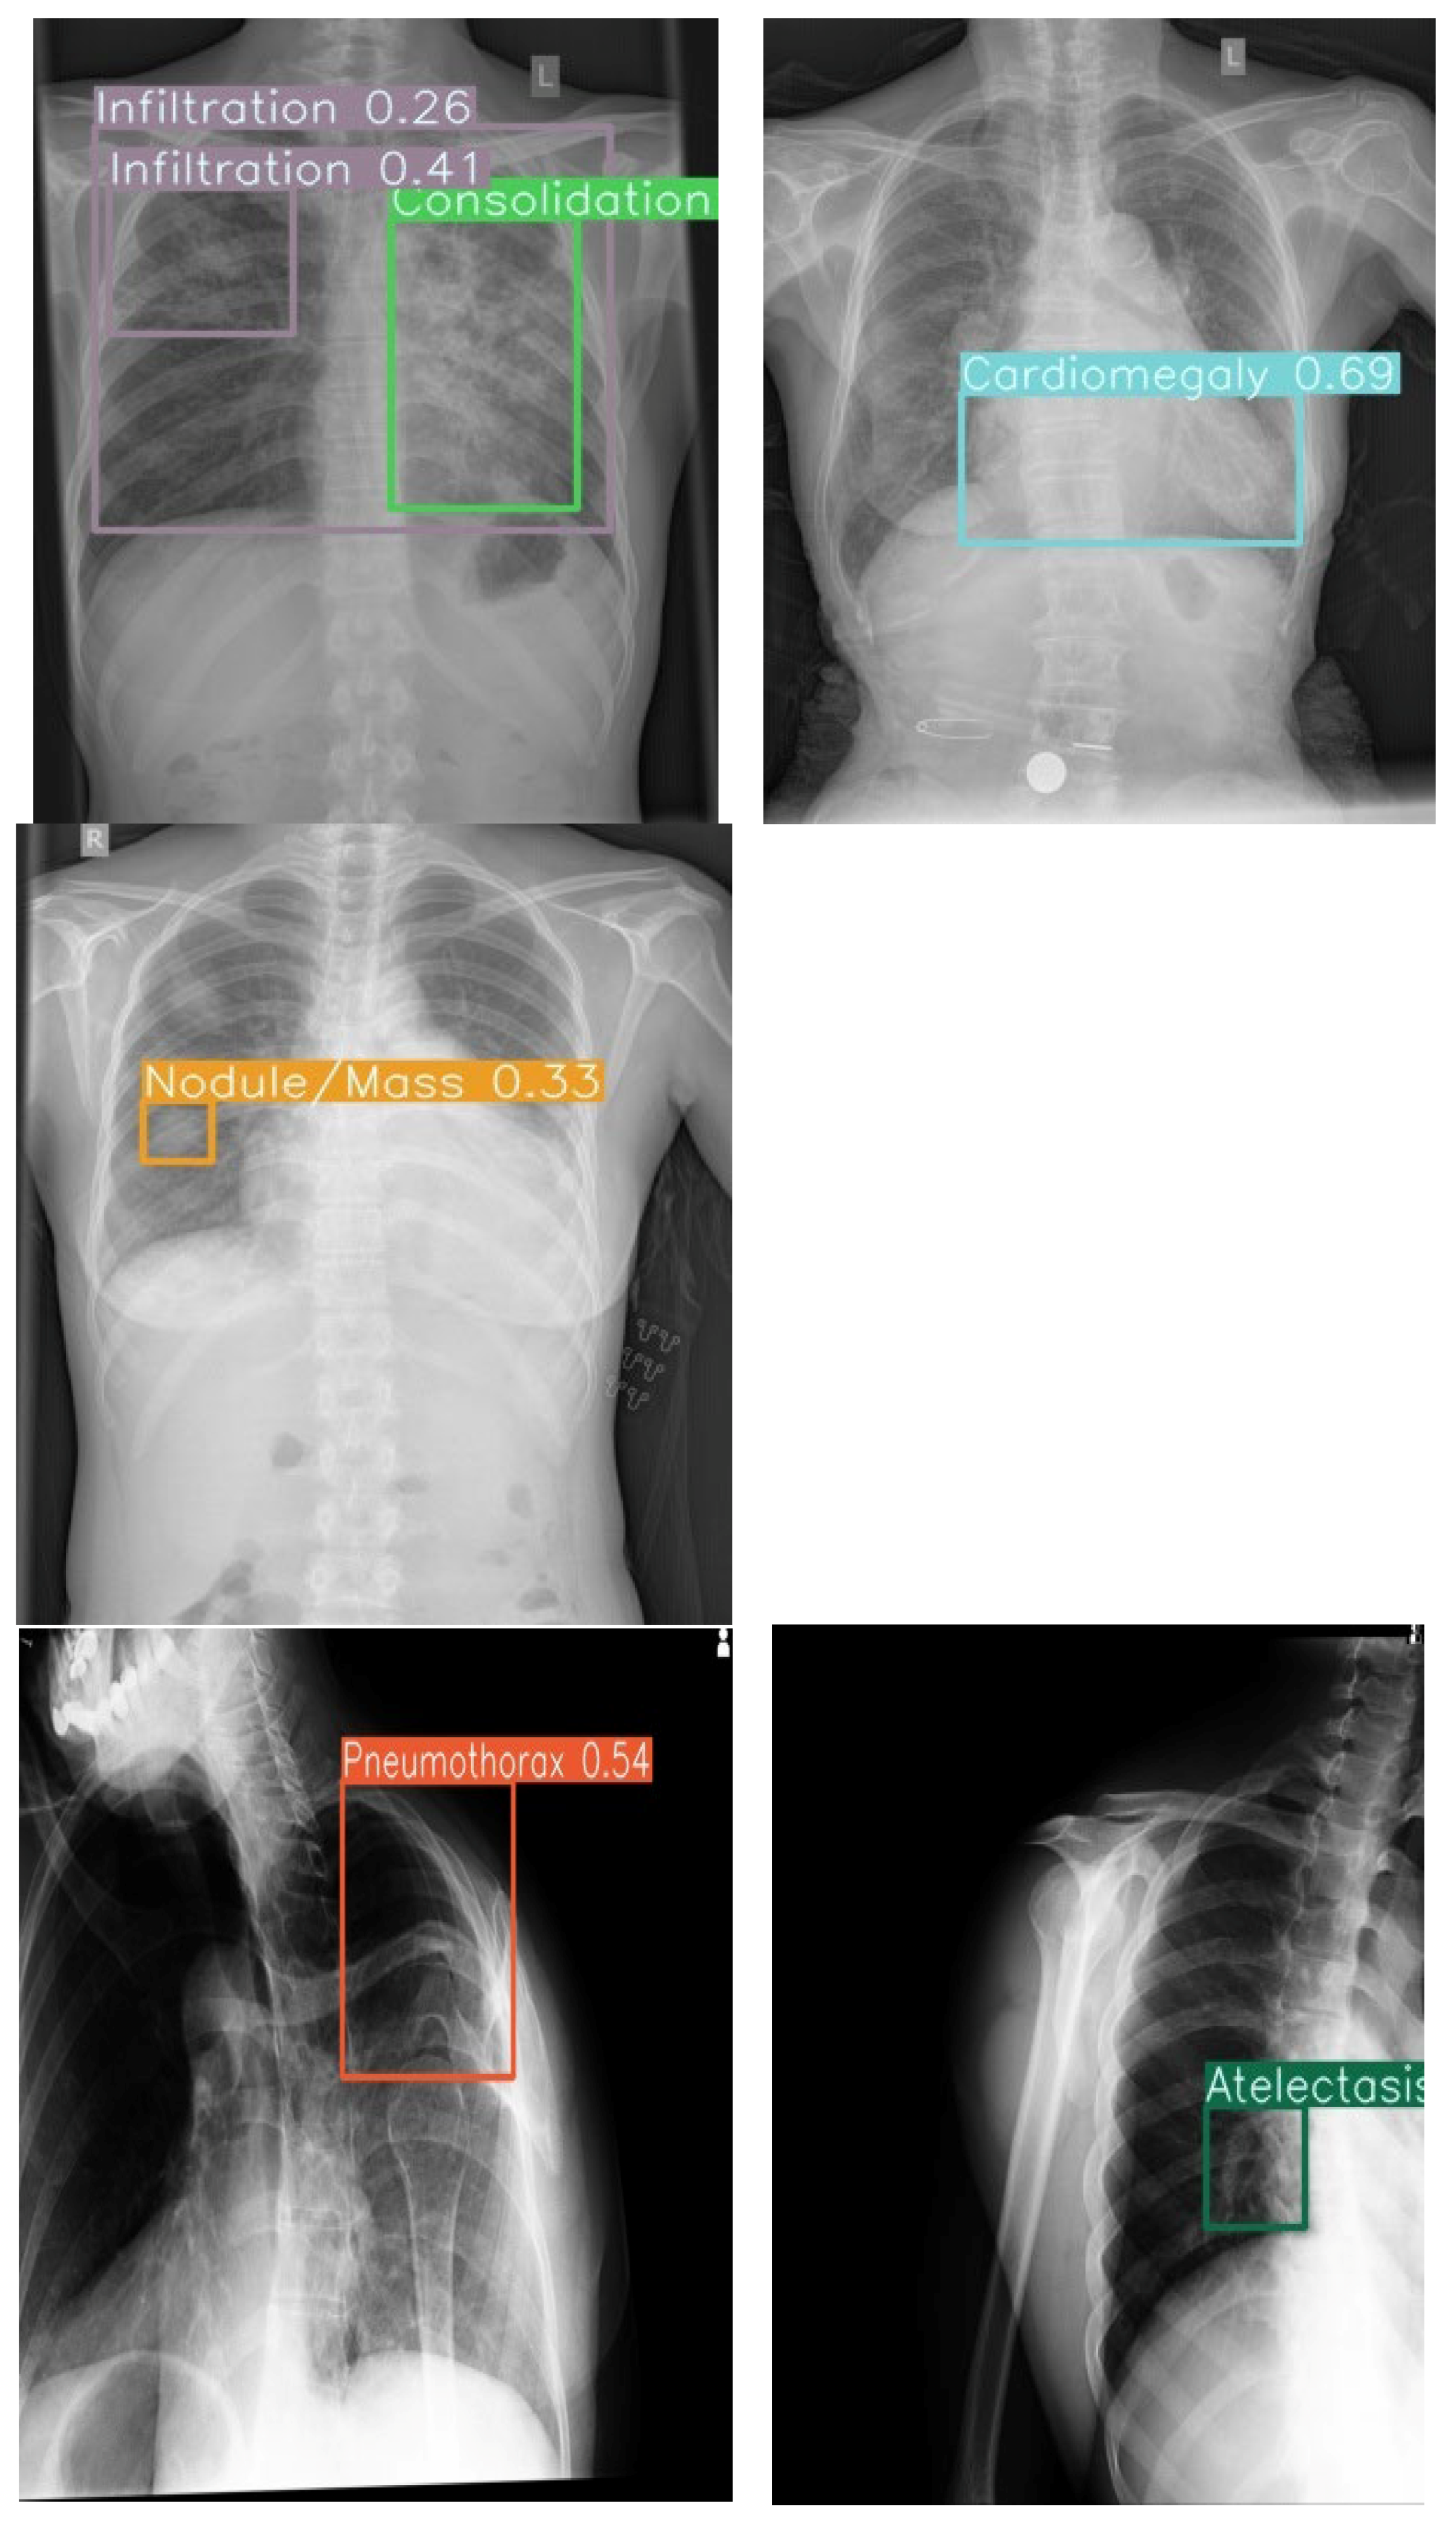

The system achieved an overall area under the receiver operating characteristic curve (AUC) of 0.86, indicating strong discriminatory ability. Model sensitivity reached 68%, while specificity was maintained at 99%. The mean average precision (mAP) of 0.93 confirmed adequate localization capabilities for the bounding box predictions across all pathology classes (Figure 3 and Figure 4).

4.2. Co-Occurrence Detection and Visualization

The model effectively identified singular and multiple co-occurrences of pathologies in one X-ray. The unique 14-color bounding box system provided immediate visual differentiation, enabling rapid interpretation of different pathologies in a single X-ray. Confidence score overlays further enhance utility by allowing prioritization of high-certainty detections during time-constrained readings.

4.3. Radiologist Performance Enhancement

The uniquely color-coded detection system for 14 pathologies minimized radiologist confusion by eliminating same-color bounding box overlap, while confidence scores enabled prioritization of high-certainty findings. Integration of both lateral and frontal views further streamlined chest X-ray interpretation workflow (Figure 5).

Figure 5. Example outputs with 14-color bounding boxes on multi-pathology cases in Row 1 (Frontal view) and Row 2 (Lateral view).